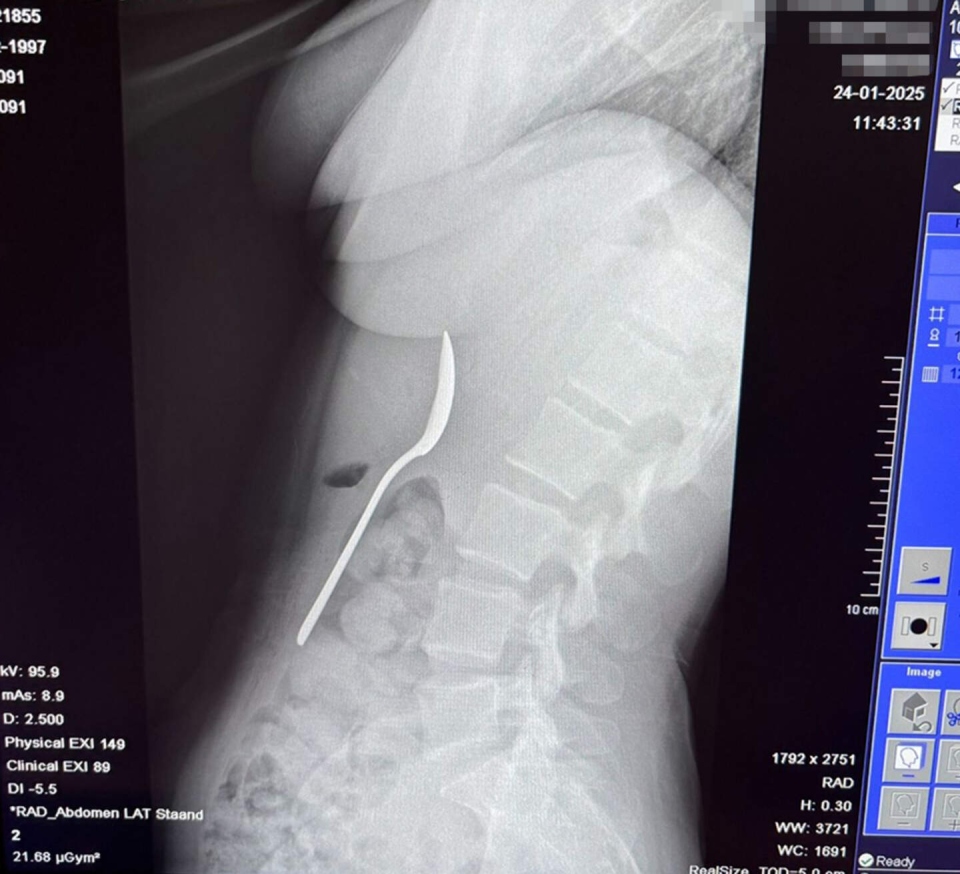

img

Hai ngày sau, dụng cụ đó được lấy ra dưới gây tê cục bộ.